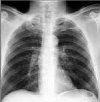

Рентген грудной клетки. Профилактический и диагностический метод рентгенологического исследования грудной полости и легких. Рентгенография грудной клетки - это скрининговое исследование по выявлению рака, туберкулеза и профессиональных заболеваний легких, рекомендованное для здоровых людей один раз в год. Флюорограммы - это изображения размером 70x70 или 110x110 менее информативные, чем стандартные рентгенограммы, но сопровождаемые меньшим воздействием радиации. В настоящее время широко применяется цифровая флюорография с низкими дозами, которая сопровождается еще более низкой нагрузкой на дозы, обеспечивая лучшее изображение, архивирование и долгосрочное хранение изображений.

Оценивая результаты флюорографии, рентгенолог оценивает состояние легочного рисунка, корней легких, плевральных пазух и тени средостения. Усиленный легочный паттерн, определяемый с помощью флюорографии, обнаруживается при остром воспалении в легких любого происхождения. Наличие фиброзной ткани в легких указывает на проникающую травму, хирургическое вмешательство, острый инфекционный процесс с исходом при фиброзе (туберкулез, пневмония). Очаговые тени в средней и нижней долях чаще указывают на очаговую пневмонию, в верхних отделах - туберкулез. Кальцификации, обнаруженные при флюорографии, служат доказательством изолированного, неразвитого очага инфекции (туберкулез, глистогонное, бактериальное) и не представляют опасности.

Уплотнение, расширение и твердость корней легких позволяет думать о пневмонии или бронхите, бронхоэктазии. Спайки и плевральные слои указывают на длительный воспалительный процесс. Состояние пазух во время флюорографии важно для определения наличия плеврального выпота во время плеврита. Расширение тени средостения в первую очередь указывает на изменения в сердце, но не имеет серьезного диагностического значения. При смещении средостения по данным флюорографии следует заподозрить накопление выпота или воздуха в плевре, крупных новообразованиях легких и немедленно направить больного к торакальному хирургу.